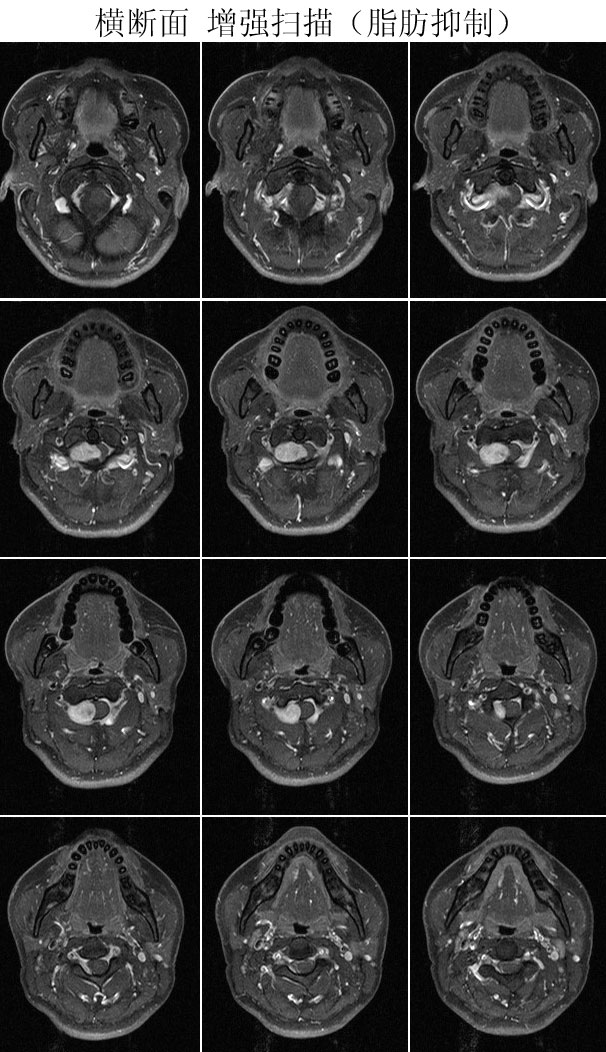

本病例来自广东同江医院

病史:女,27岁,洗头按摩时扭颈导致昏迷,检查发现颈椎占位

手术病理:

神经鞘瘤